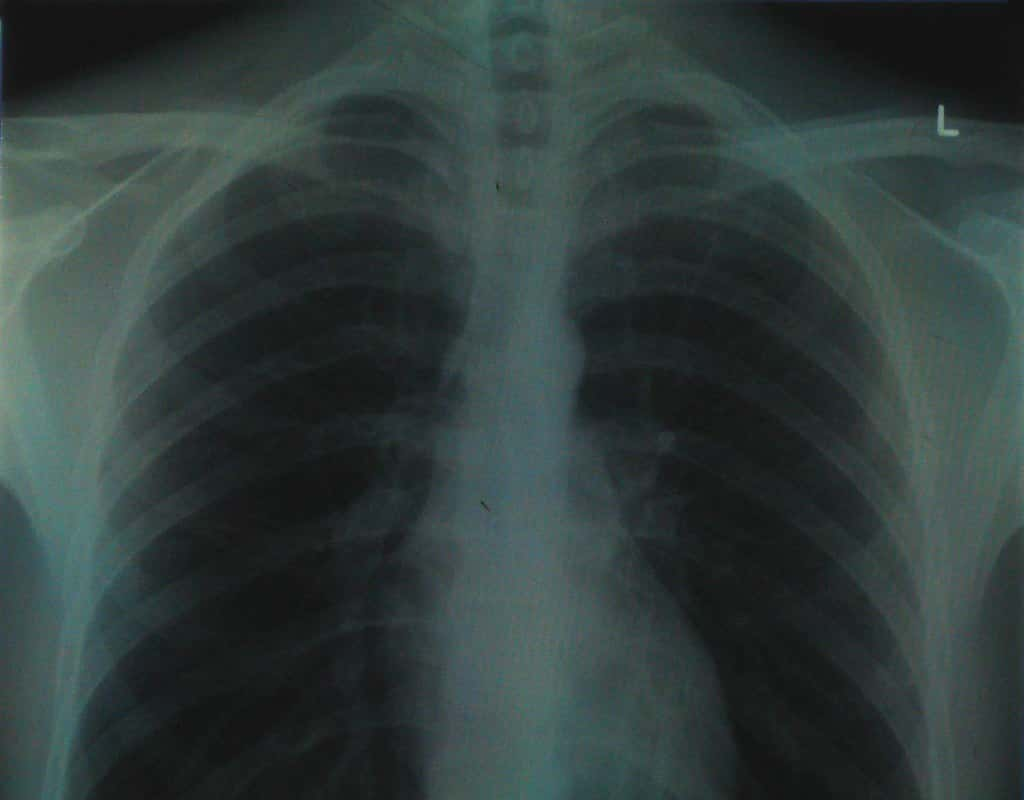

I went to the hospital with shortness of breath and my heart racing. They did a chest X-ray, a blood test for blood clots, an ECG, and a few other tests but they all came back normal. After observing me overnight, everything still looked good: oxygen saturation was perfect, my heart rate was still a bit elevated but nothing too crazy, and it seemed that it was likely leftover symptoms from a bad virus that I'd had a week or so earlier.

The ER doctor asked me how I would feel if they sent me home and I just had a bad feeling about it all. I told him as such and that I had no real basis for it except that I just felt off about it. He said: "Fair enough, let's try one more test and if that comes back negative, then we'll send you up to General Medicine and see if they can track something down."

That test was a VQ scan that found despite all other tests showing no results for blood clots, I actually had a whole bunch of them in both lungs. I ended up with a diagnosis of unprovoked bilateral pulmonary embolisms and I am on blood thinners for life. Super grateful both for the bad feeling and the ER doctor who was willing to listen to it!

There is a legit nursing diagnosis called "Sense of Impending Doom: that is in reference to a gut feeling. Someone can't explain what is wrong and there's nothing obvious, but we need to take it seriously. The body somehow feels something wrong when the brain can't find the words. I've found this to be very common with pulmonary emboli, heart attacks, and strokes. The body is so weird...